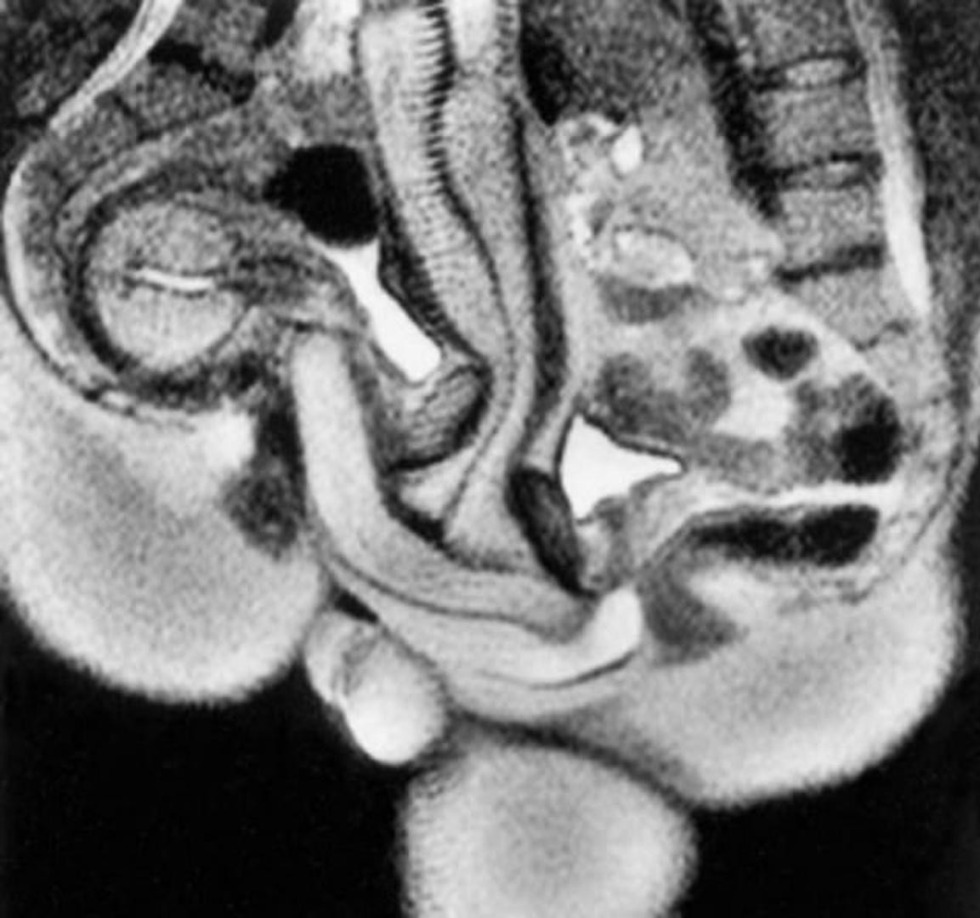

Penis in the vagina in the section

Intercourse in the section

Anatomy of sexual intercourse in the section